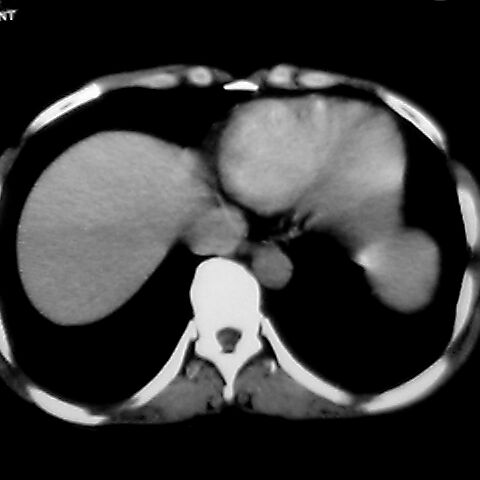

女 48岁 食道癌术前体检发现脾占位。

脾胀内部巨大低密度肿块,边界清或不清,中心坏死,轻度增强,内见散在钙化,结合食道癌病史多考虑:转移癌.

脾脏低密度灶伴钙化,增强化明显,中心见液化坏死灶,强化延时明显。考虑血管瘤。转移瘤待排。

1肝右下叶小囊肿2右肾上极囊肿或错构瘤3脾脏不典型血管瘤可能性大.

1,脾血管瘤。2,右肝,右肾小囊肿。